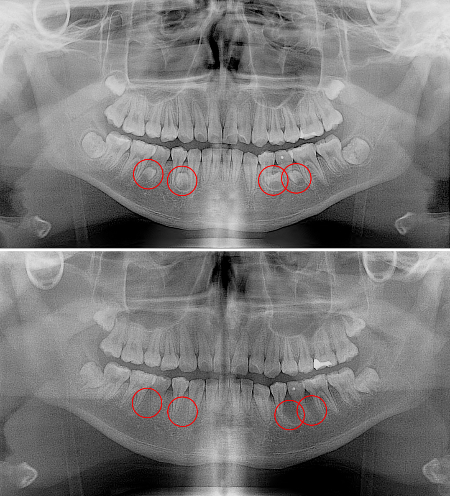

일반적으로 사람의 구강에는 28개의 영구치와 4개의 사랑니가 나와 총 32개의 치아가 자란다. 이보다 더 많거나, 불필요한 치아가 추가로 생기는 경우를 과잉치라 한다. 정확한 원인은 밝혀지지 않았지만 부모나 형제에게 과잉치가 있으면 발생 확률이 높아지는 것으로 보고된다. 대부분 턱뼈 내에 매복돼 있어 보호자는 물론 당사자조차 모르는 경우가 많다.

과잉치는 '구강 내 시한폭탄'으로 비유될 만큼 다양한 구강 문제를 일으킨다. 치아의 정상적인 맹출(치아가 잇몸 속에서부터 잇몸을 뚫고 올라오는) 과정을 방해하기 때문이다. 특히 영구치가 자리 잡는 6~15세 사이에는 더욱 주의해야 하는데, 앞니가 나오는 것을 방해해 앞니가 아예 못 나오거나 이상한 위치로 나오는 부정교합을 유발할 수 있기 때문이다. 턱뼈에 매복한 과잉치가 제거되지 않고 오랫동안 남아있게 되면 주변에 낭종을 유발하기도 한다.

과잉치는 파노라마 방사선 촬영과 근단 방사선 사진 촬영, CT 촬영 등을 통해서만 발견할 수 있다. 발치가 가장 좋은 치료법이지만 그렇다고 무턱대고 뽑아서는 안 된다. 아무리 조심하더라도 주변 치아들에 영향을 줄 수 있기 때문이다. 그래서 과잉치가 인접 영구치의 맹출에 크게 영향을 줄 것으로 예상되면서 주변 치아의 치근이 어느 정도 성숙한 후 발치를 결정하게 된다.